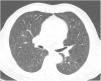

Case reportA 69-year-old man, with history of hypertension and dyslipidemia, was diagnosed with high-grade bladder urothelial carcinoma (pT1). A transurethral resection of the bladder was performed, followed by mensal BCG intravesical instillation in the last 18 months, without major adverse reactions except flu-like symptoms lasting less than 48 h after each dose. Two days after the last instillation, he presented macroscopic hematuria and severe fatigue, sweating and persistent non-productive cough. Eight days later, due to the persistence of symptoms and the appearance of dyspnea and fever, he went to the emergency department. He had no recent sick or tuberculosis contacts. On admission, he was febrile (38.3 °C), hypotensive (89/40 mmHg), in respiratory distress with inspiratory crackles in both lungs. Arterial blood gas analysis showed, in ambient air, hypoxemia [partial pressure of oxygen 63 mmHg) and respiratory alkalosis. Laboratory tests revealed mild anemia (hemoglobin 11.9 g/dL) with normal white blood cell and platelet count, increased levels of C-reactive protein (10.9 mg/dL) and erythrocyte sedimentation rate (57 mm/h), acute kidney injury [serum creatinine (sCr) 2.35 mg/dl], hematuria, leukocyturia and proteinuria. Serological tests were negative for hepatitis B and C and human immunodeficiency virus. Markers of immune-mediated disease (antinuclear, antineutrophil cytoplasmic, antiglomerular basement membrane and anti-streptolysin O antibodies) were all negative. Serum immunoglobulins and complement levels were normal. The chest radiography showed a bilateral reticulonodular infiltrate (Fig. 1) and the thoracic computed tomography (CT) demonstrated a diffuse pulmonary micronodulation, in a miliary pattern (Fig. 2). Renal ultrasonography revealed normal-sized kidneys with a reduced corticomedullary differentiation. Specimens for microbiological exam were collected and empirical broad-spectrum antibiotic treatment was started. On the fifth day of treatment, both fever and acute respiratory failure persisted, lung opacities were unmodified and renal function worsened (sCr 3.52 mg/dL). Multiple cultures of sputum, urine and blood were negative for both bacteria and mycobacteria, including polymerase chain reaction (PCR). A bronchoscopy with bronchoalveolar lavage (BAL) was performed which revealed a prevalence of lymphocytes (48.2%) and an elevated CD4/CD8 ratio (11), absence of malignant cells and bacteriological and mycobacteriological exams were negative. Due to the lack of clinical and imagiological improvement, the diagnosis of disseminated BCG infection was suggested and empiric anti-tuberculosis treatment (ATT) [isoniazid 300 mg, rifampin 600 mg and ethambutol 1200 mg; once daily] associated with a corticosteroid (prednisolone 60 mg once daily) was started and, few days later, patient’s clinical condition improved, with sustained apyrexia, resolution of acute respiratory failure and slow but steady recovery of renal function. He was discharged in good general condition and continued ATT for 6 months. Steroids were discontinued tapering down the dosage for 5 months. A high-resolution CT scan of thorax, performed 6 months after discharge, showed almost complete resolution of the lung opacities with a reduction in the number and size of bilateral pulmonary nodules (Fig. 3) and kidney function was fully recovered (sCr 0.86 mg/dL). BCG immunotherapy was discontinued. No sign of relapse was observed after one year of follow-up.